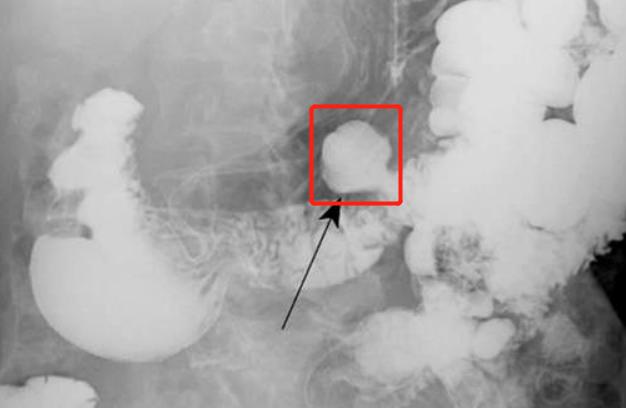

简单来说,憩[qì]室是出现在肠道里的"小鼓包"。(下图红圈位置就是一个小憩室)

多数情况下它不会有什么症状,但憩室发生炎症时,就会导致患者出现腹痛、腹胀、腹泻等症状。憩室炎主要好发于老年人或长期便秘的人群。